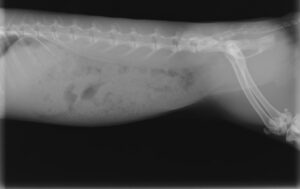

そして、入院し、治療した翌日のレントゲンが下です。

胃のサイズが小さくなっているのがわかると思います。

このまま退院し、通院にて数週間で完治しました。